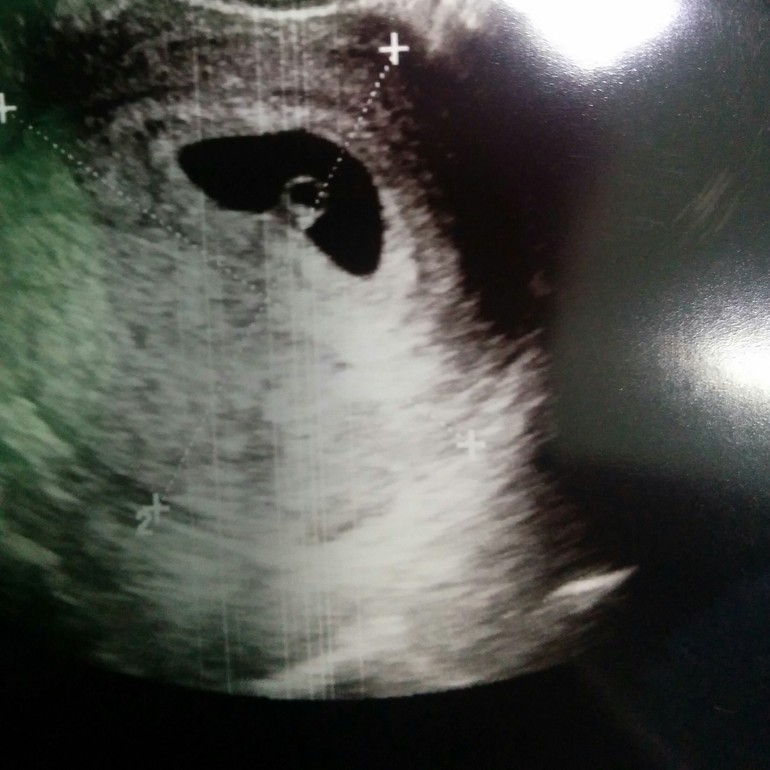

первое узи в 6 недель

Срок у меня от последних м 6 недель и 2 дня.

По узи моя крошка соответствует 6 неделям, сердечко стучит, размер эмбриончика 4,5 мм.